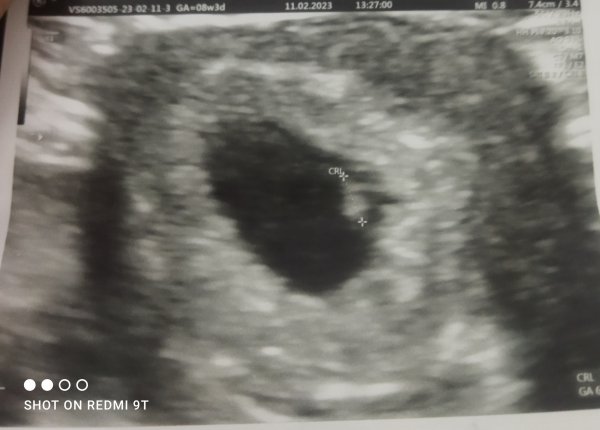

Suda var benim elim titriyor galiba netlestiremiyorum. Aslında şuan çok net fakat yükleme esnasında mi bulaniklasiyor anlamadım.

Selamlar, malesef üzerinde tahmin yapılamayacak kadar kötü, ilerleyen zamanlarda yenisi gelir ise atarsınız. Sevgiler. ( bulanık anlaşılmıyor )